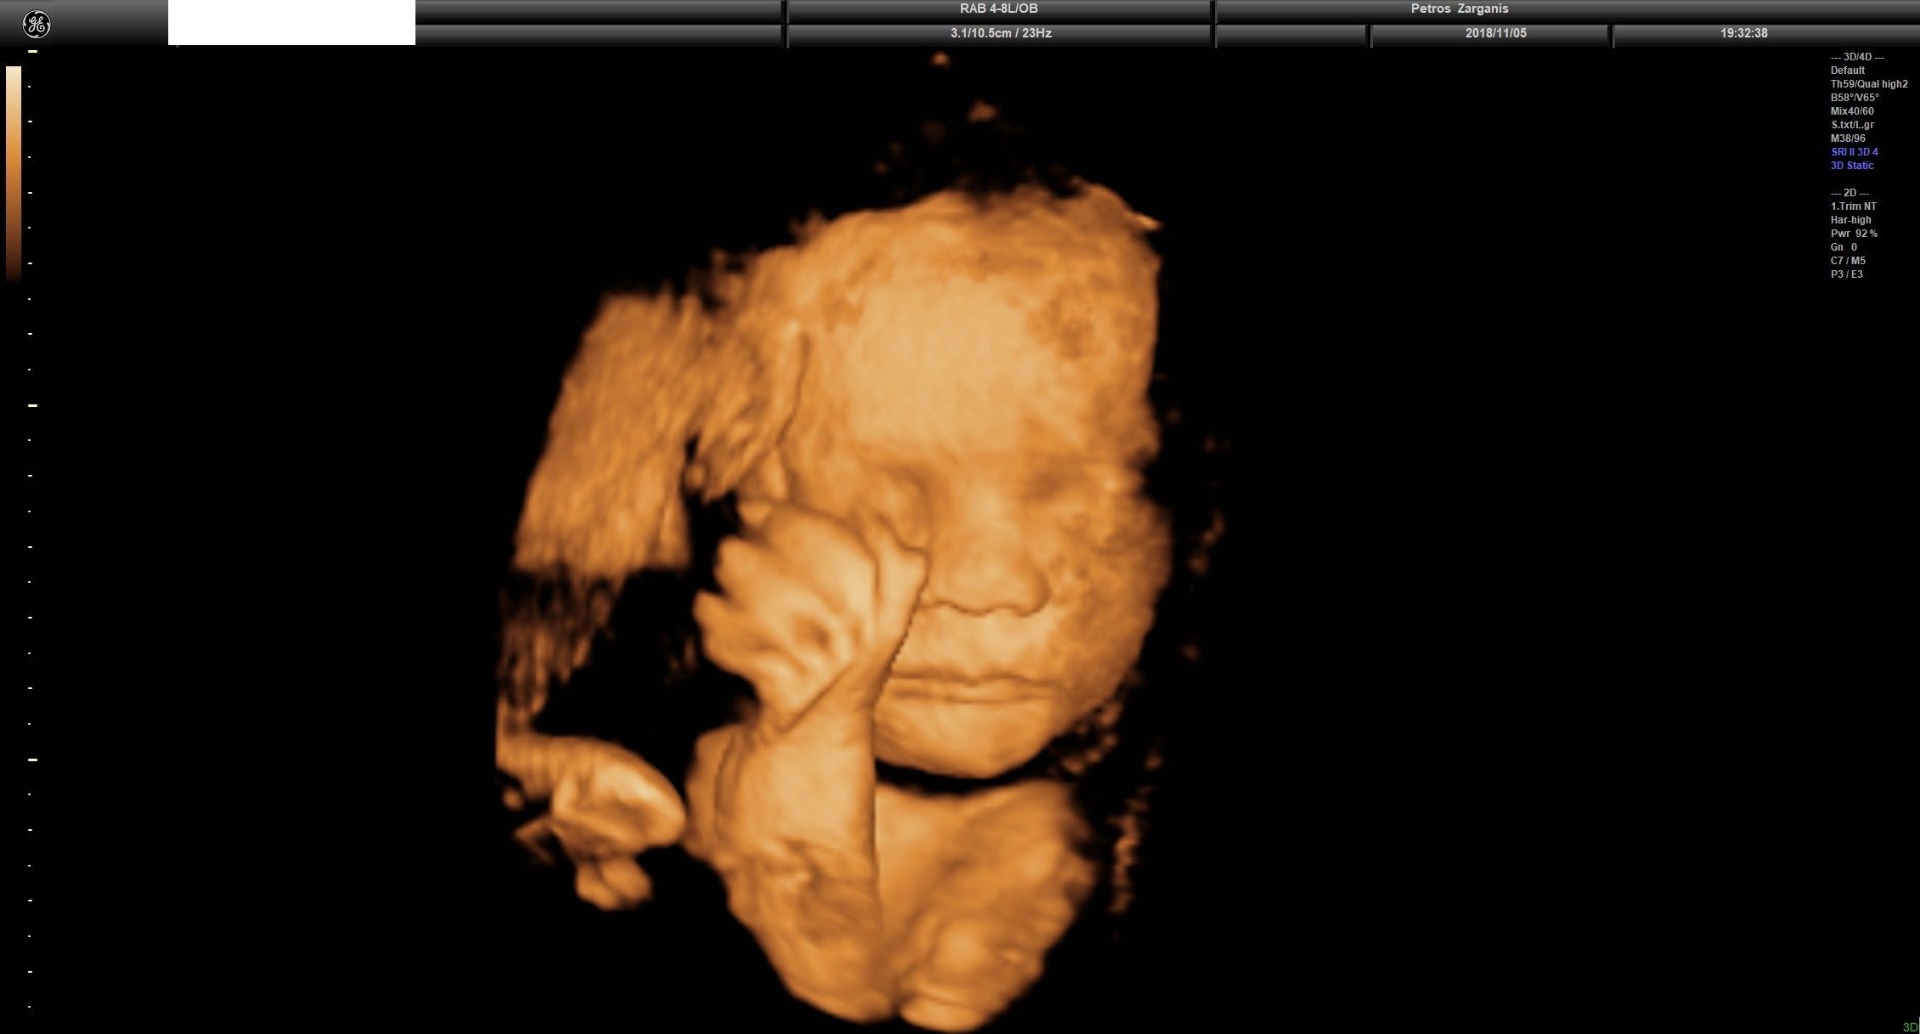

Το μαιευτικό υπερηχογράφημα ή προγεννητικό υπερηχογράφημα σήμερα αποτελεί τυπικό μέρος της προγεννητικής φροντίδας σε πολλές χώρες, καθώς μπορεί να παρέχει σημαντικές πληροφορίες σχετικά με την υγεία της μητέρας, το χρόνο και την πρόοδο της εγκυμοσύνης, καθώς και την υγεία και την ανάπτυξη του εμβρύου. Αν και οι υπέρηχοι είναι συνηθισμένοι σήμερα, η τεχνολογία υπερήχων δεν ξεκίνησε επίσημα στην ιατρική μέχρι τα μέσα της δεκαετίας του 1950.

Κατά τη διαδικασία του μαιευτικού υπερηχογραφήματος χρησιμοποιείται ιατρικός υπέρηχος για τη δημιουργία οπτικών εικόνων σε πραγματικό χρόνο του αναπτυσσόμενου εμβρύου στη μήτρα. Μπορούμε να ορίσουμε τον υπέρηχο ως τα ηχητικά κύματα με πολύ υψηλή συχνότητα, πάνω από το εύρος της ακουστικής συχνότητας, τα οποία δεν μπορούν να γίνουν αντιληπτά από το ανθρώπινο αυτί, κάτι αντίστοιχο δηλαδή με τα UV στο οπτικό πεδίο.

Ο Ian Donald ανακάλυψε με τη μελέτη του ότι διαφορετικοί ιστοί αντιδρούν διαφορετικά στους υπερήχους, παρέχοντας πληροφορίες. Έτσι κατέληξε στο συμπέρασμα ότι η ανάπτυξη ενός μελλοντικού μωρού μπορεί να παρακολουθείται μέσω υπερήχων. Η νέα τεχνολογία έγινε αποδεκτή αρκετά εύκολα και ξεκίνησε να χρησιμοποιείται στην κλινική μαιευτική από τις αρχές της δεκαετίας του 1960.

Η πρώτη ακριβής ανίχνευση της καρδιακής δράσης του εμβρύου, χρησιμοποιώντας υπερήχους, αναφέρθηκε και τεκμηριώθηκε το 1972. Στα τέλη της δεκαετίας του 1970, η χρήση υπερήχων έγινε σχεδόν ουσιαστικό μέρος της φροντίδας που παρέχεται στις έγκυες γυναίκες και τα έμβρυά τους, καθώς με διάφορες μετρήσεις μπορούσε να πετύχει πρώιμες διαγνώσεις εμβρυϊκών ανωμαλιών. Ένα υπερηχογράφημα εμβρύου μπορεί να βοηθήσει τον ιατρό να εντοπίσει μια εγκυμοσύνη εκτός της μήτρας (έκτοπη κύηση), να προσδιορίσει την ηλικία του εμβρύου και να προβλέψει την πιθανή ημερομηνία τοκετού.

Φυσικά, οι εξελίξεις και οι βελτιώσεις του υπερηχογραφήματος εμβρύου συνεχίστηκαν και κατά την επόμενη δεκαετία, από το 1980 έως το 1990. Στη δεκαετία του 1980 εισήχθη η πρώτη τεχνολογία 3D υπερήχων, αλλά μόλις το 1986 λήφθηκε η πρώτη τρισδιάστατη εικόνα ενός εμβρύου. Αργότερα, στη δεκαετία του 1990, έκανε το ντεμπούτο της η τεχνολογία 4D υπερήχων, η οποία δείχνει και κίνηση.